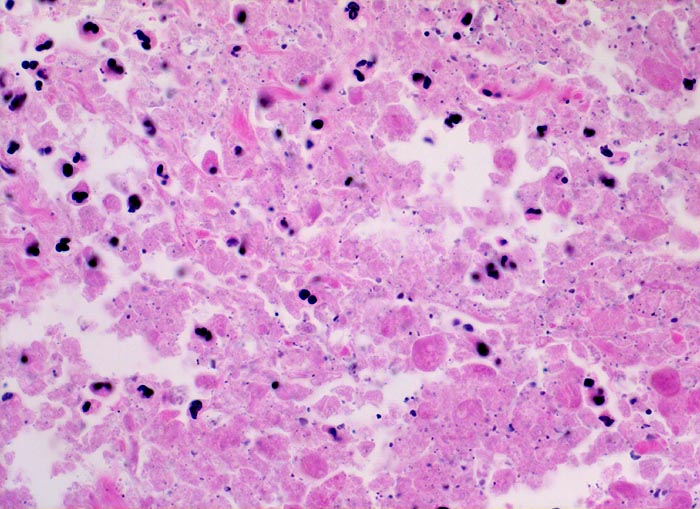

Morphologische Merkmale:

• Multiple Fragmente einer transurethralen Resektion.

• In der Mitte oben ist ein Harnblasenfragment mit tumorfreien Anteilen der Harnblasenwandmuskulatur erkennbar. Dieses Fragment ist bedeckt von einem aus wenigen Zellagen bestehenden dyskohäsiven Urothel, von dem sich einzelne Zellen ablösen. Die Zellkerne sind pleomorph, hyperchromatisch und vergrössert(Carcinoma in situ des tumorfernen Urothels).

• Fragmente eines papillär aufgebauten Karzinoms.

• Tumorzellkerne mit ausgeprägter Pleomorphie und Hyperchromasie sowie prominenten Nukleolen. Fehlende polare Ausrichtung der Tumorzellen. Zahlreiche Mitosen und Apoptosen.

• Kleinherdige Tumornekrosen.

• Invasion der Lamina propria (Tumorfragmente links): Kleine Tumorzellgruppen oder Einzelzellen haben die Basalmembran an wenigen Stellen durchbrochen und liegen in der Lamina propria.

• Begleitendes dichtes gemischtes Entzündungsinfiltrat.